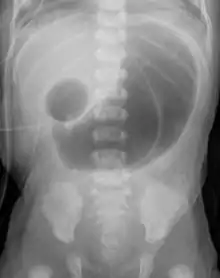

Radiograph with double bubble sign indicating duodenal atresia

If not diagnosed in utero, infants with intestinal atresia are typically diagnosed at day 1 or day 2 after presenting with eating problems, vomiting, and/or failure to have a bowel movement.[3] Diagnosis can be confirmed with an X-ray, and typically followed with an upper gastrointestinal series, lower gastrointestinal series, and ultrasound.[5][3]